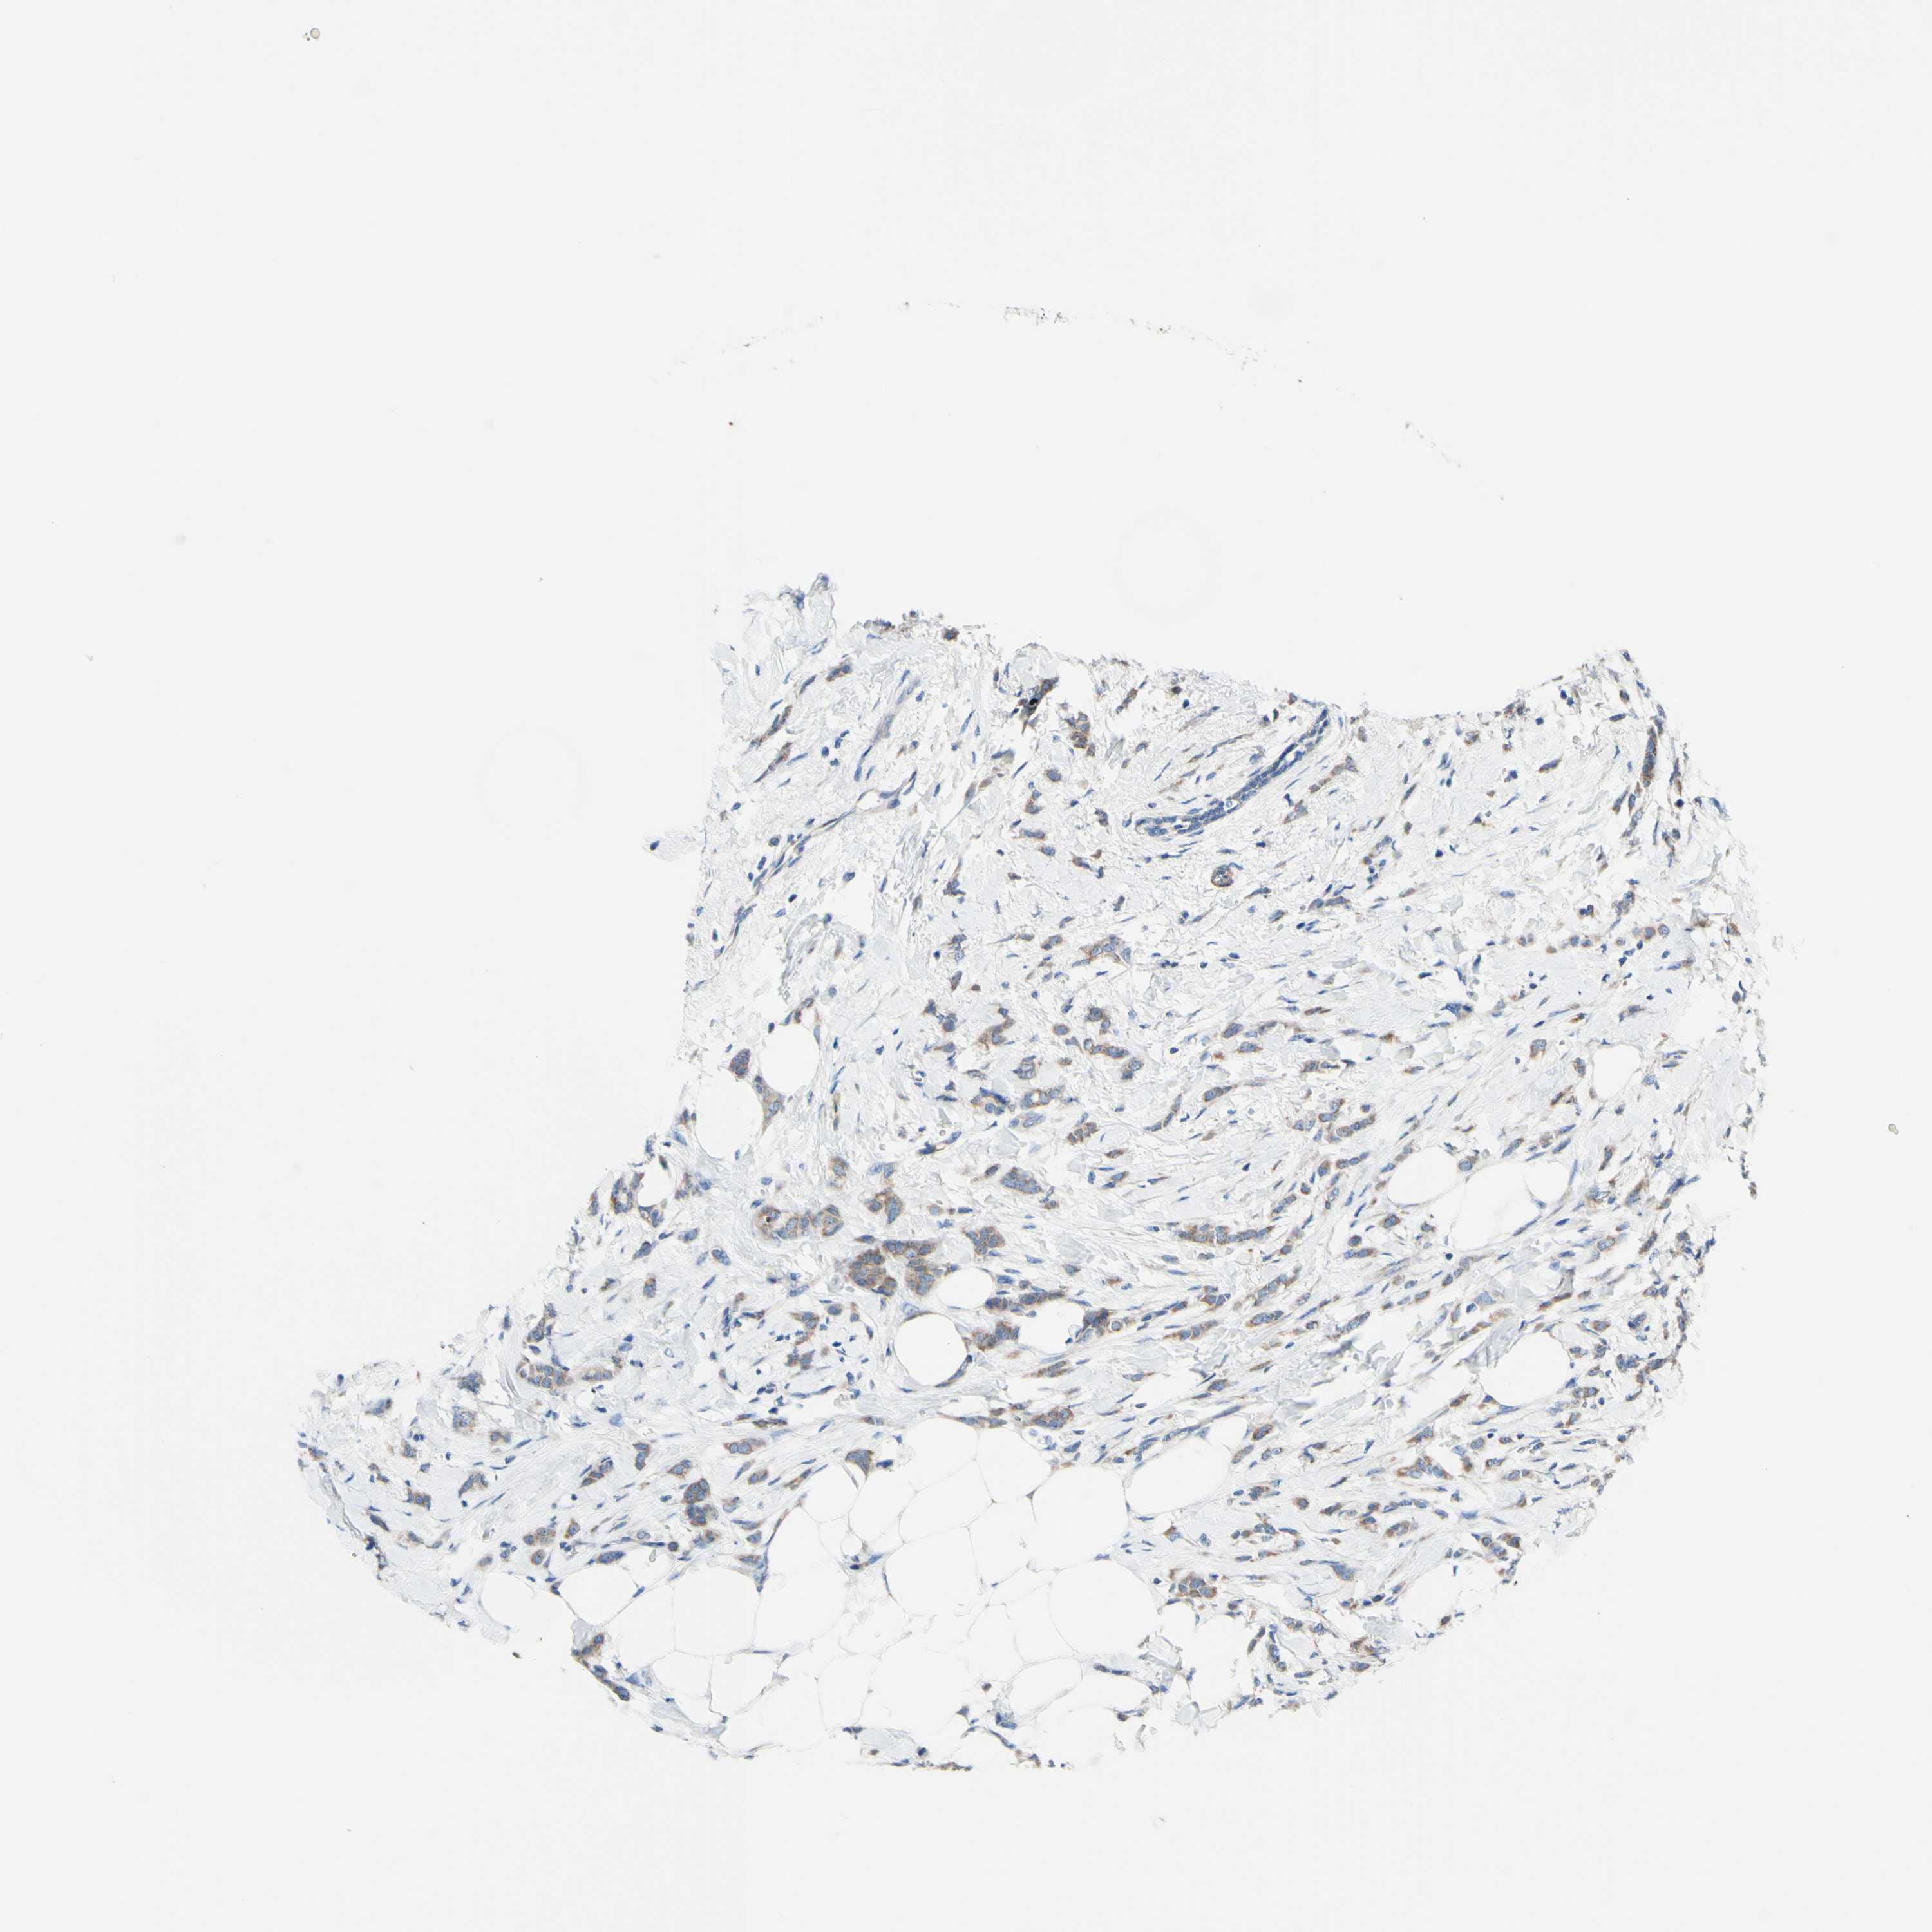

CANCER BREAST CANCER Show tissue menu

BRCA TCGA BRCA VALIDATION PROTEIN EXPRESSION